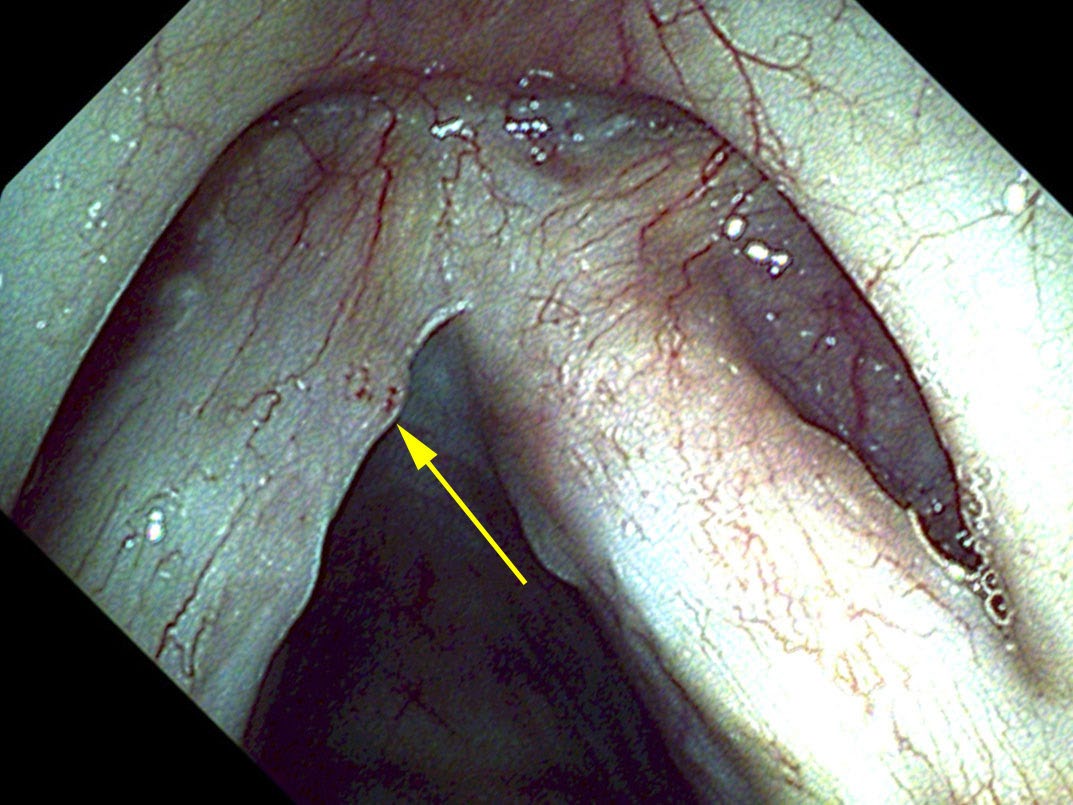

With new high-definition endoscopes and video processors that selectively highlight the red in blood vessels, papilloma can now be fairly accurately identified endoscopically in the office. Small amounts of papilloma can also be treated in the office by ablation with a laser such as the pulsed KTP laser, which may be passed through a channel in the endoscope. The energy from the pulsed KTP laser is selectively absorbed by blood vessels and since all papilloma have a large central vessel they are particularly susceptible to destruction by this laser.